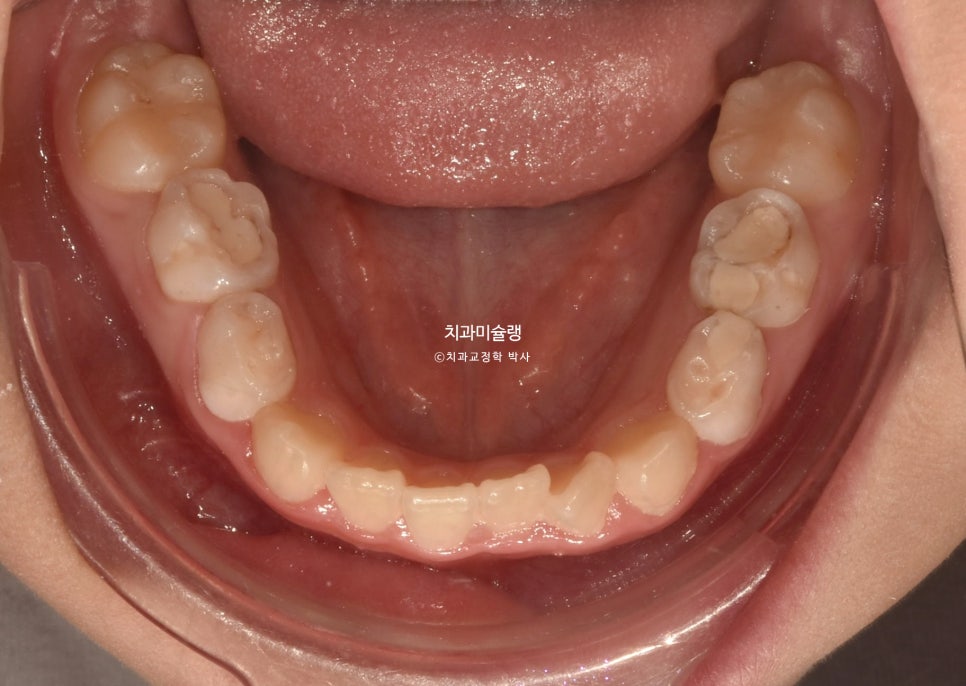

2024년 6월 초진 상태

24년 6월, 교정치료를 위해 내원한 만 10세 어린이 입니다.

송곳니 덧니와 개방교합이 보입니다.

배열은 가지런히 정돈되었네요. 그사이 남아있던 유치가 빠지고 영구치가 올라오고 있습니다.